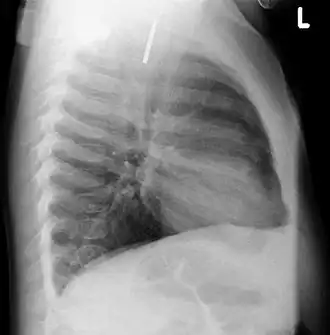

Chest radiograph showing a Venezuelan 25 cent coin lodged in the upper esophagus of a 9-year-old girl. -

A coin seen on lateral CXR in the esophagus -